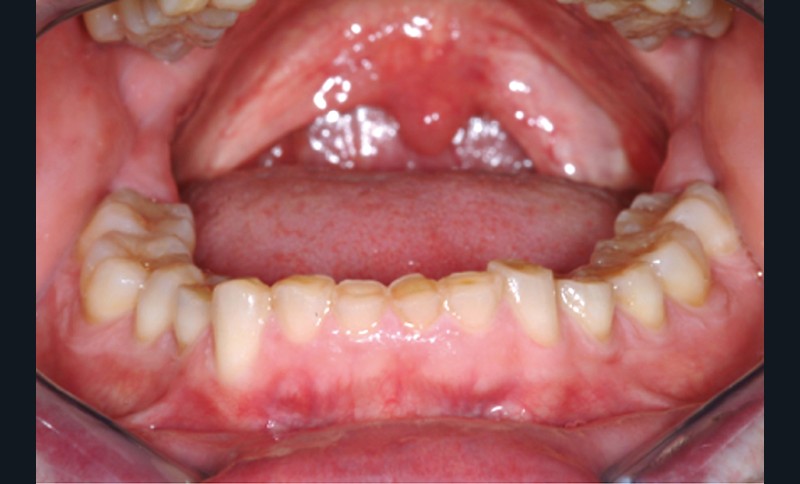

Jean-Pierre Attal : Exactement, car il est possible d’appliquer le protocole de la technique « 3 steps » aux patients présentant des pertes de substance d’origine attritive (bruxisme) (fig. 5).